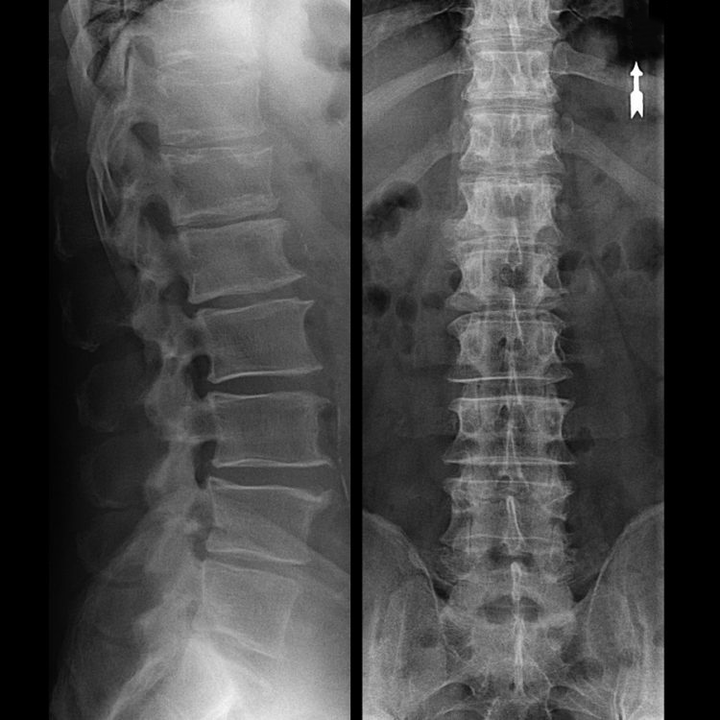

osteocondroza regiunii vertebrale la radiografie

În cazuri tipice, osteocondroza coloanei vertebrale cervicale și cervico-toracice apare așa cum este descris mai sus. Prin urmare, etapa principală a diagnosticului a fost și rămâne identificarea plângerilor pacientului, stabilirea prezenței spasmului muscular concomitent prin simpla palpare a mușchilor de-a lungul coloanei vertebrale. Este posibil să se confirme diagnosticul de osteocondroză folosind examenul cu raze X?

O „radiografie” a coloanei cervicale și chiar și cu teste funcționale pentru flexie și extensie, nu arată cartilaj, deoarece țesutul lor transmite raze X. În ciuda acestui fapt, pe baza locației vertebrelor, se pot trage concluzii generale despre înălțimea discurilor intervertebrale, îndreptarea generală a curburii fiziologice a gâtului - lordoză, precum și prezența excrescentelor marginale pe vertebre cu iritarea prelungită a suprafețelor acestora de către discurile intervertebrale fragile și deshidratate. Testele funcționale pot confirma diagnosticul de instabilitate la nivelul coloanei cervicale.

Deoarece discurile în sine pot fi văzute numai folosind CT sau RMN, rezonanța magnetică și tomografia computerizată cu raze X sunt indicate pentru a clarifica structura internă a cartilajului și a formațiunilor cum ar fi proeminențele și herniile. Astfel, cu ajutorul acestor metode se face un diagnostic cu acuratețe, iar rezultatul tomografiei este o indicație, și chiar un ghid de actualitate, pentru tratamentul chirurgical al unei hernii în secția de neurochirurgie.